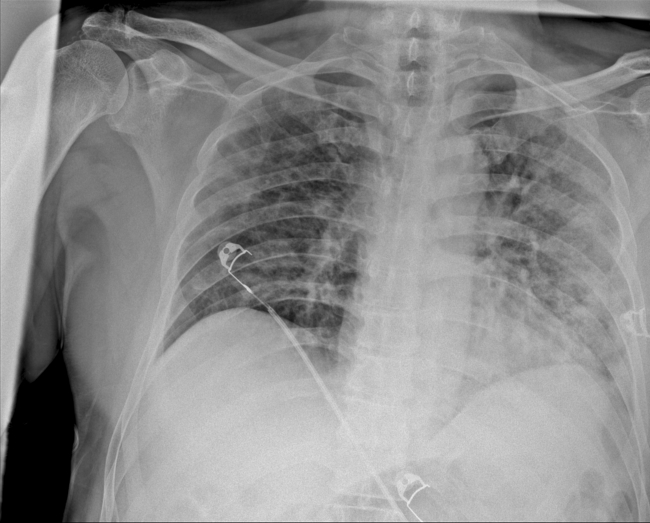

Koronavirüsün akciğerdeki ağır tahribatı tomografi görüntülerine yansıdı

Akciğerlerde tutuluma yol açarak, solunum yetmezliği, nefes darlığı ve zatürreye sebep olan koronavirüsün bu organa verdiği hasar, hastalığın yol açabileceği zararları gözler önüne serdi.

Ankara Şehir Hastanesinde COVID-19 tedavisi gören hastalara ait akciğer görüntülerine ulaşıldı. Görüntülerde, hastalığın ne kadar hızlı ilerlediği ve akciğerleri nasıl tuttuğu ortaya çıktı.

Prof. Dr. Karalezli, koronavirüs tedavisi gören hastalara ait akciğer görüntülerinden hastalığın yol açtığı tahribatı ve hastalar üzerindeki etkileri anlattı.

Tedavisine rağmen nefes darlığı şikayetleri devam eden bir hastaya uygulanan akciğer görüntülemesinde hastanın her iki akciğerinin büyük bir bölümünü enfeksiyon kapladığını tespit ettiklerini ifade eden Karalezli, "Bu hastalığın sonunun ne olduğunu bilmiyoruz. Akciğer tutulumları, bu şekilde olduğu zaman hastaları oksijen tedavisi ile gönderiyoruz. Çok yeni bir hastalık olduğu için bu seyir nasıl olacak? Geriye dönüş var mı? Takiplerle öğrenebileceğimiz bir durum." dedi.

Normal akciğer görüntüleri ile koronavirüs hastalarının akciğer görüntüleri arasında ciddi farklar bulunduğunu belirten Karalezli, şu bilgileri verdi:

"İnsanların aradaki farkları anlamaları için her iki akciğer görüntülerine de yer verdim. Görüntülerdeki beyazlıklar akciğerdeki tutulumu gösteren görüntüler ne yazık ki. Bu hastalar yoğun bakım hastaları. Filmler birbirine az çok benzeyen şekilde. Altta yatan hastalığı olanlarda ise daha kötü seyrediyor."

Kliniğe yeni başvuran bir hastanın, 5 Ağustos'ta çekilen tomografi görüntülerindeki tipik koronavirüs görüntülerinin olduğunu ifade eden Karalezli, hastanın bir hafta içerisindeki tomografi görüntüsünde ciddi değişiklik olduğunu ve enfeksiyonun çok arttığını söyledi.